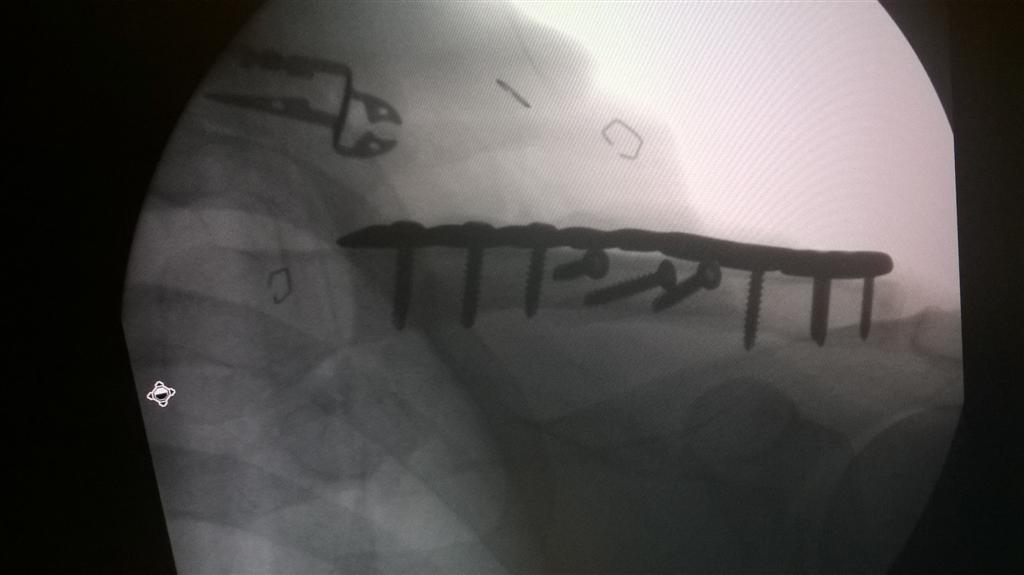

this doesn't rank against Joostio's femur break, but it's my first broken bone -- took 51yrs to get there ... some shots for the archives ... cycling crash about a week ago.

That's some nice metal you got in there! Ouch! I'm 6 months out since break and surgery, walking with a limp but the leg is getting stronger. Almost tried sailing last weekend. Very soon I hope. Broken bones suck! At least I will be ready for ski season. I've been doing a lot of fishing this summer and I did surf twice. Can't wait to ride my bike, sailboard and ski again. Been too long. I should see if I can post pics of my latest 2 breaks. The femur was in April, right wrist 2 years ago. I had external fixation for the wrist, pretty freaky lookin. Good health to all!

Mountain Biking eh? Looks like they forgot some bike parts in you. I don't think you need to worry about that derailleur in the left-top of the image. Good to have spares when out riding...